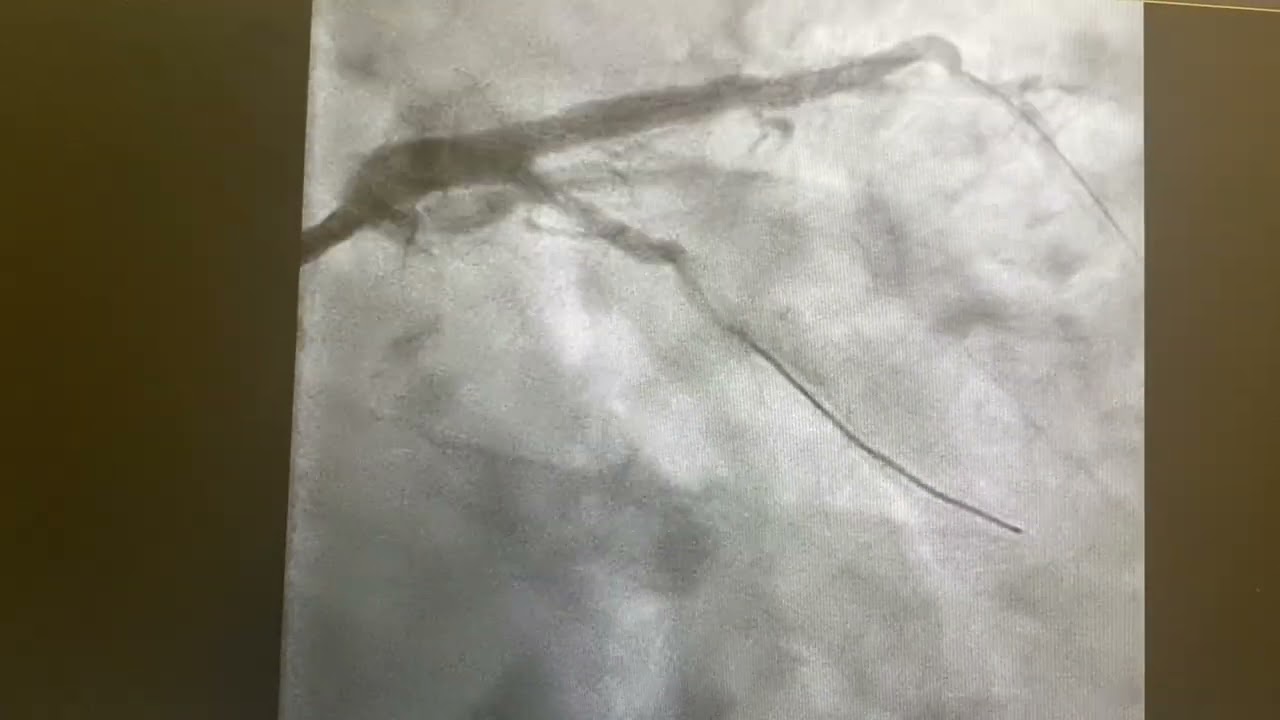

63 years old male presented with NSTEMI, in the last 24 hours suffered from 3 attacks of chest pain accompanied with sweating

Unstable ruptured plaque in left main coronary artery, severe thrombotic stenosis of LAD

Provisional stenting did it well